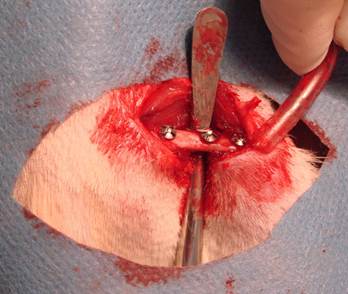

Figure 3

Placement of miniscrews

After the drilling and the miniscrew placement (Figure 3), muscle and fascia layers were closed with simple resorbable 4.0 sutures (Vicryl 4-0, Ethicon) and finally the skin incisions were closed with continious 3.0 sutures (Silk 3.0, Dogsan). Postoperative antibiotics (gentamicin, 0.5 mg/kg) and analgesics (xylocaine 0,5 mg/kg) were given subcutaneously. The positions of the miniscrews were controlled by cone beam CT scanning. During post-operative period, all of the animals were controlled day by day and none of them were lost.